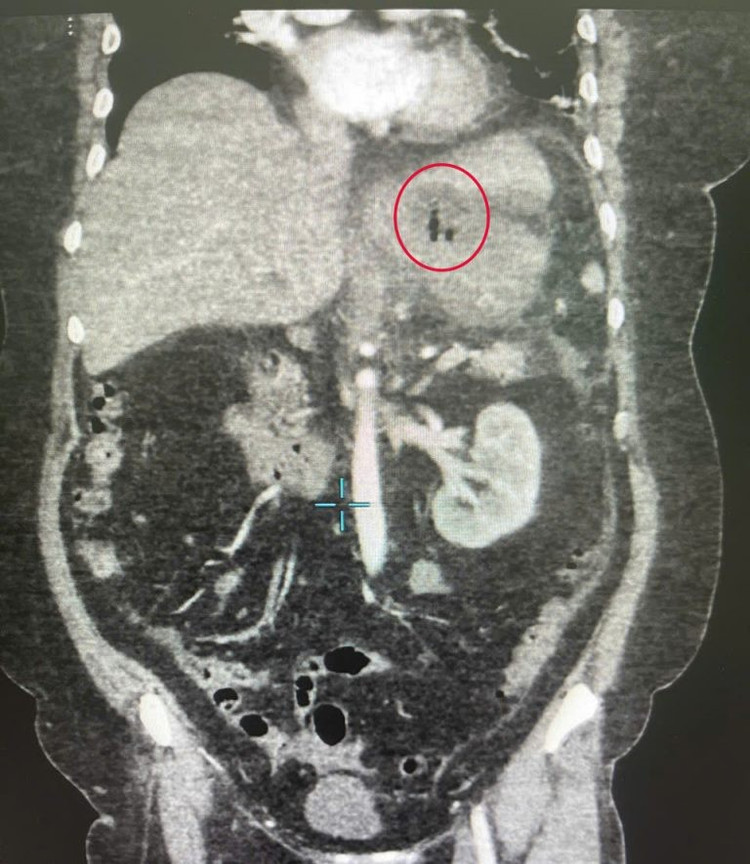

Hình ảnh cận lâm sàng cho thấy xương cá trong dạ dày - Ảnh BVCC

Sau hội chẩn khẩn giữa các bác sĩ khoa Ngoại Tổng quát và ê-kíp trực cấp cứu, bệnh nhân được chỉ định mổ cấp cứu. Ban đầu, các bác sĩ định thực hiện phẫu thuật nội soi. Tuy nhiên, do tổn thương nằm sâu, giả mạc bao quanh, dịch mủ đặc và nhiều dính, phẫu thuật nội soi gặp khó khăn nên phải mổ hở.

Ca mổ được thực hiện bởi các bác sĩ khoa Ngoại tổng quát, với sự dẫn dắt của BS.CKII Lê Tòng Bá, Phó Trưởng khoa. Qua đường mổ dài khoảng 15cm trên rốn, các bác sĩ phát hiện một ổ áp xe lớn phía mặt sau bờ cong nhỏ dạ dày, chứa nhiều mủ trắng đục.

Khi bóc tách ổ áp xe, các bác sĩ đã phát hiện một chiếc xương cá dài khoảng 4cm đâm xuyên qua thành dạ dày. Đây chính là “thủ phạm” gây thủng và tạo ổ mủ kéo dài suốt thời gian qua.